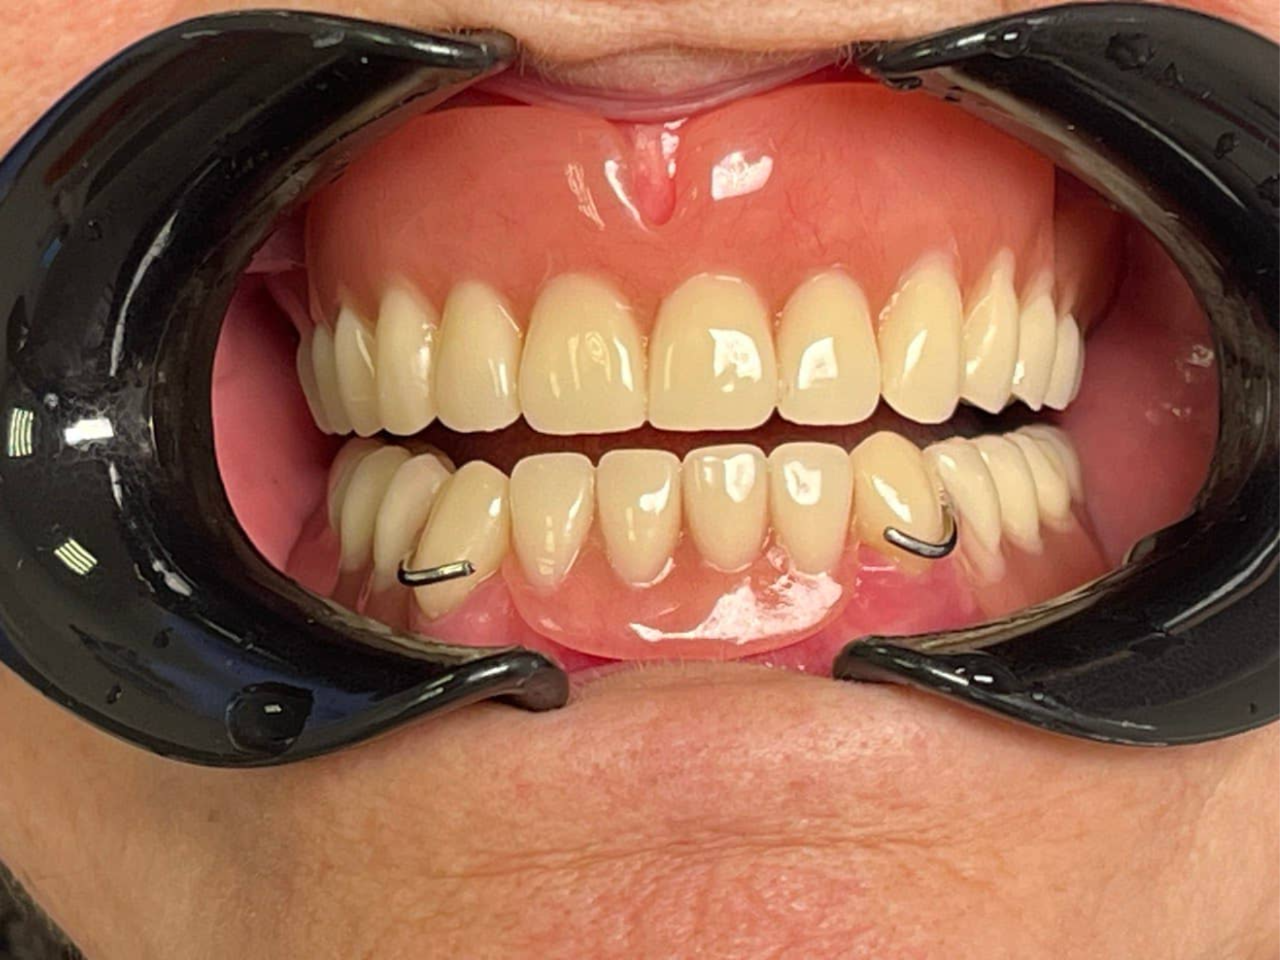

После

Результат лечения

Изготовлен полный съёмный протез на верхнюю челюсть (базис из акриловой пластмассы, искусственные зубы).

Протез удерживается за счёт:

• анатомического прилегания к протезному ложу;

• клапанного механизма (краевого прилегания);

• адгезии (прилипания) к слизистой оболочке.

Несмотря на почти полное отсутствие зубов, два сохранённых клыка были использованы как естественные опоры. Конструкция:

• Частичный съёмный протез замещает отсутствующие зубы.

• Фиксация: металлические или акриловые кламмеры (удерживающие элементы) охватывают клыки, обеспечивая надёжную стабильность протеза во время жевания и речи.

• Клыки выступают в роли «естественных крючков» — они предотвращают смещение и выпадение протеза.

По завершении протезирования пациент получил:

• восстановление зубного ряда на обеих челюстях;

• возможность нормально пережёвывать пищу (в рамках возможностей съёмных протезов);

• улучшение дикции — речь стала чётче;

• эстетическую реабилитацию — улыбка выглядит естественно, губы поддерживаются протезами, овал лица восстановлен;

• уверенность в себе — пациент перестал стесняться общения и фотографий;

• отсутствие хирургических вмешательств и длительной реабилитации.

Пациент отметил: «Я уже не надеялся, что смогу нормально есть и улыбаться. Клыки, которые остались, стали моим спасением — протез держится отлично».